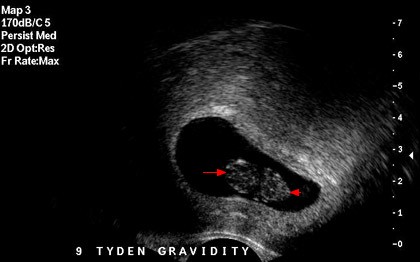

To, že budu mít velké problémy s otěhotněním, vím již léta. Paní gynekoložka mi totiž diagnostikovala polycistické vaječníky. Léta mám problémy s pravidelnou me...